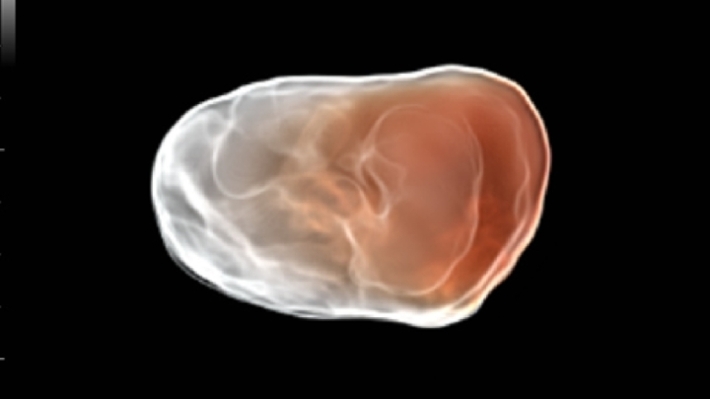

УЗИ-аппарат Mindray DC-70 — это современная ультразвуковая система экспертного класса, предназначенная для проведения диагностических исследований в различных областях медицины, включая кардиологию, акушерство и гинекологию, абдоминальные и сосудистые исследования. Аппарат сочетает высокое качество изображения с широким набором функциональных возможностей, что делает его эффективным инструментом для диагностики.

• Многофункциональность: Поддержка различных режимов сканирования, включая 2D, 3D/4D, цветное допплеровское картирование и другие, позволяет использовать аппарат для широкого спектра медицинских задач;

• Smart 3D™ — получение трехмерного (3D) ультразвукового изображения методом «свободной руки»;

• iLive™ — технология 3D/4D-визуализации с функцией постобработки изображений;

Изображения